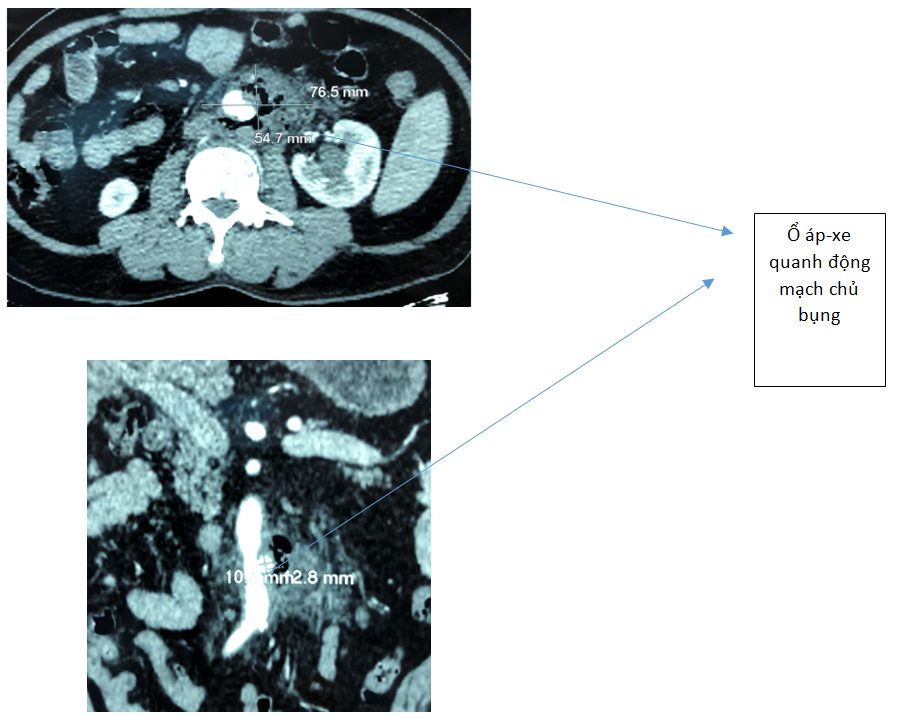

Người bệnh được chụp CT-scan có bơm cản quang. Kết quả hình ảnh cho thấy động mạch chủ bụng bị thủng 1 lỗ đường kính khoảng 2cm, tạo thành túi phình giả quanh động mạch chủ kích thước lớn, đường kính 6,5cm kéo dài 8,8cm. Các bác sĩ chẩn đoán đây là một trường hợp nhiễm trùng sau phúc mạc, ổ nhiễm trùng ăn thủng động mạch chủ bụng dưới thận tạo thành túi phình giả, nguy cơ vỡ khiến người bệnh tử vong bất cứ lúc nào. Bệnh nhân cần được gấp rút phẫu thuật thay đoạn động mạch chủ bị thủng do nhiễm trùng.

Nhóm bác sĩ phẫu thuật Tim- Mạch máu của Bệnh viện Bình Dân đã hội chẩn khẩn cấp để tìm hướng điều trị cho người bệnh đang trong tình trạng nguy kịch, túi phình dọa vỡ, có nhiều khối áp-xe trong ổ bụng. Thêm vào đó, bệnh nhân có tiền sử nhiều bệnh nền phức tạp bao gồm đứt động mạch chủ bụng do tai nạn lúc còn trẻ, viêm gan, xơ gan, đái tháo đường nên mọi chỉ định y khoa đều cần sự cân nhắc rất kỹ càng. Các bác sĩ cho biết, việc dùng ống ghép nhân tạo là không khả thi vì khối tổn thương nằm trong môi trường nhiễm trùng, nguy cơ nhiễm trùng phát triển và khả năng thải ghép cao. Sau khi hội chẩn, các bác sĩ thống nhất chọn mảnh ghép bằng màng ngoài tim bò đã qua xử lý để thay thế vào đoạn động mạch đã hư hại.